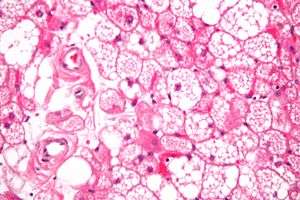

| Micrograph of a hibernoma. H&E stain. | |

The tumors histologically resemble brown fat. There are four histologic types recognized, but one is the most frequently seen (typical). There is a background of rich vascularity.

- Lobular type: Variable degrees of differentiation of uniform, round to oval cells with granular eosinophilic cells with prominent borders, alternating with coarsely multivacuolated fat cells (pale cells). There are usually small centrally placed nuclei without pleomorphism. The cells have large cytoplasmic lipid droplets interspersed throughout.[1][2]

- Myxoid variant: Loose, basophilic matrix, with thick fibrous septa, and foamy histiocytes

- Lipoma-like variant: Univacuolated lipocytes, with only isolated hibernoma cells

- Spindle cell variant: Spindle cell lipoma combined with hibernoma